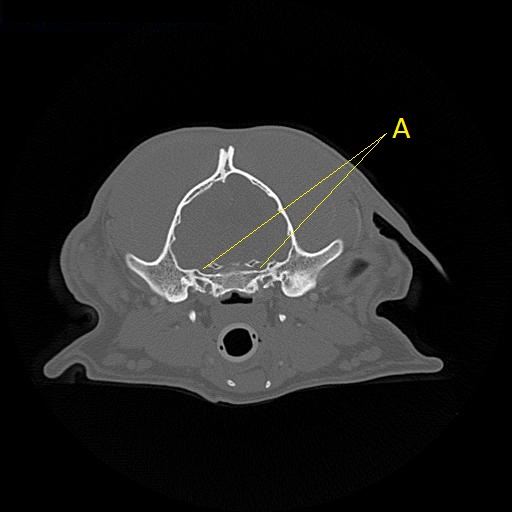

Q. Identify the structure labeled below:

A. Canal for the trigeminal nerve